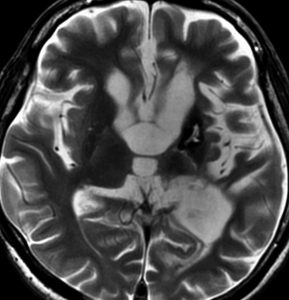

MRI

- 治療の前に必ずガドリニウム造影剤を使って全部の脳と脊髄を検査します

10歳くらいから身長の伸びが遅くなって,12歳で食欲低下と体重減少がありました。左のMRIはガドリニウム造影MRIで,視床下部と下垂体を侵す神経下垂体ジャーミノーマです。CTでは小さな石灰化(白い点)がみえます。CT検査は不必要なものでした。

ジャーミノーマ(胚腫)のMRI診断

germinomaのMRI所見は,ガドリニウム像強T1強調画像で強く増強されることです。しかし,嚢胞性変化を伴うことも少なくないし,大きな多房性の腫瘍となることもあります。MRI上では一見境界明瞭に見えますが,実際には画像でみえなくともかなり広範に周囲へ浸潤していることが多いので限局性腫瘍とは考えてはいけません。それが手術摘出だけあるいはガンマナイフなどの定位照射で治らない理由です。

germinomaが好んで発生し浸潤する部位は,松果体,視床下部,下垂体柄,下垂体後葉,下垂体前葉,視床,終板,第3脳室壁,側脳室壁の特に前角,前交連,大脳基底核,脳梁膝部,中脳視蓋,第4脳室壁 (obex),海綿静脈洞,蝶形骨洞斜台などです。これらは直接浸潤であり,播種あるいは転移ではありません。

時に脳室上衣に沿って脳室壁へ広範に浸潤する特徴があります。この脳室上衣下浸潤 subependymal infiltration は,初期には高解像度 3-tesla MRIでも描出できませんが,進行すると脳室壁に結節状の多発病変として描出されてきます。